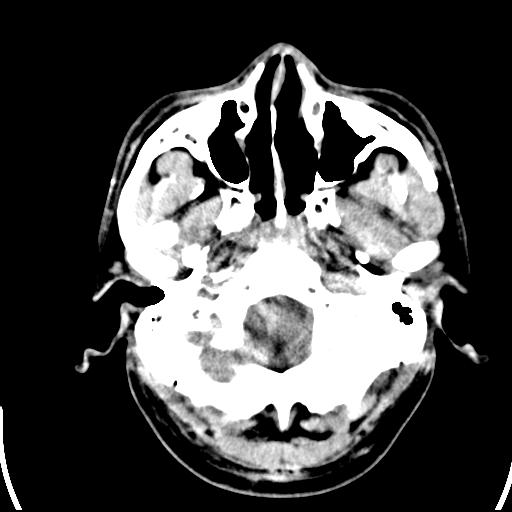

标题: CT25435:头皮下高密度影???

头皮下高密度结节影???临床上在老年男性比较常见。大家看看是什么?成因是? 本例患者,男性,51岁。外伤来诊。无染发史及发根植入史。